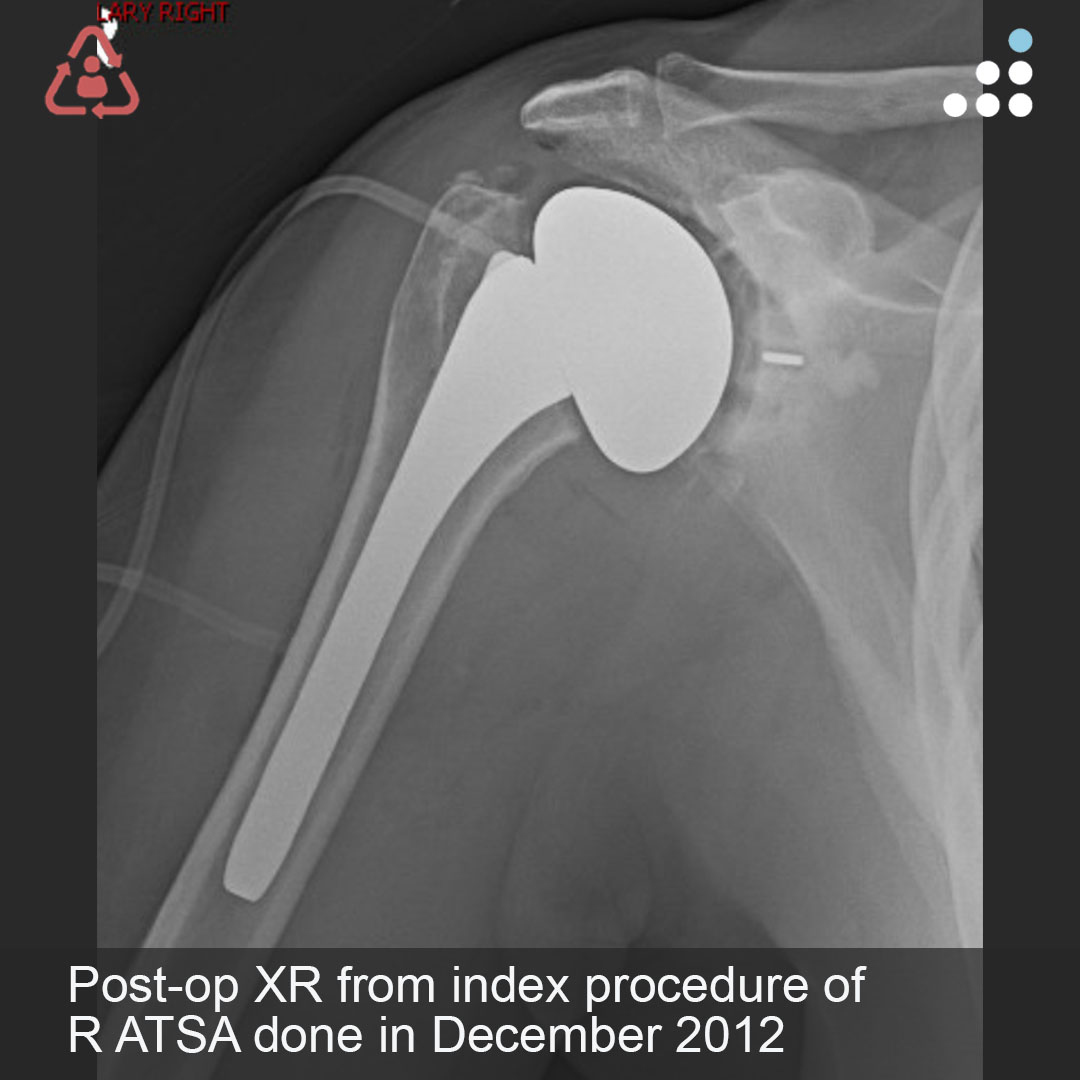

@orthobullets @KPSCALnews @rkh_md @DrMarecek @DeformityDoc @jamesablairMD @FractureDoc @stevemchale @traumaticum @DrFraneNicholas I am concerned about the +Fleck/flake sign. Get MRI or ultrasound to rule out a triceps rupture. If torn, I would perform ORIF and Triceps repair, after restoring the underlying metabolic issues. If the triceps is not torn, then would treat non-operatively.